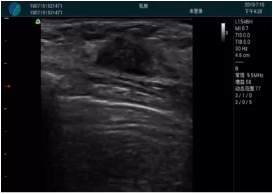

清晰顯示腺體內低回聲快影,邊界清晰,包膜較光滑

確定進針路徑并實時監(jiān)測抽吸針與腫塊位置關系

抽吸針進入腫塊內部進行旋切

抽吸過程中可見腫塊明顯縮小,并根據腫塊位置改變針道位置

抽吸旋切后再進行超聲復查,原腫塊區(qū)域未見殘留組織及出血